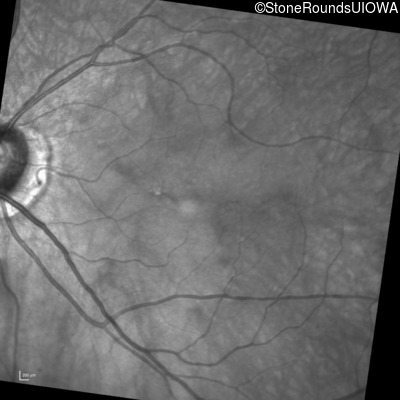

Infrared Fundus Photograph - Left - 20/400

Exemplar